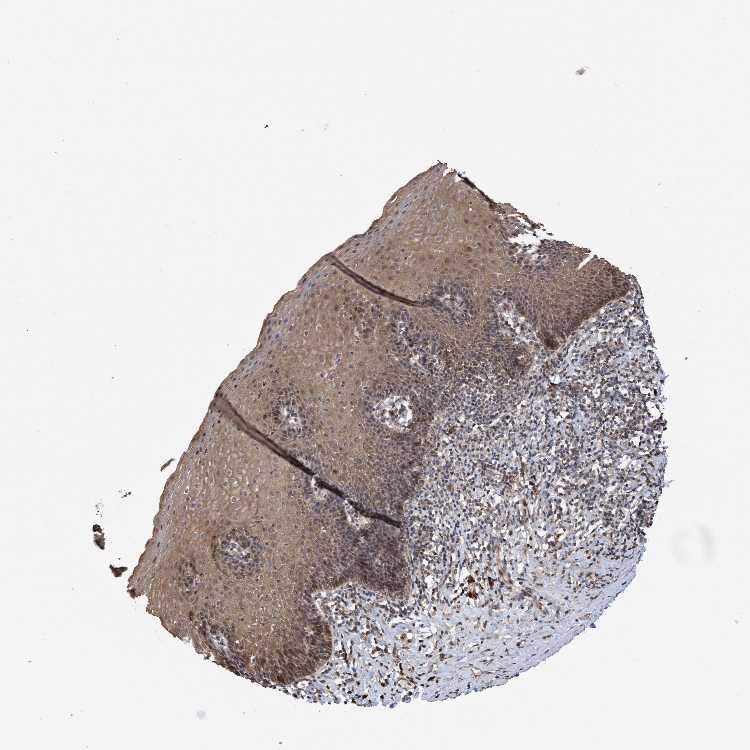

ESOPHAGUS - Antibody stainingi

Antibody staining in the annotated cell types in the current human tissue is reported as not detected, low, medium, or high, based on conventional immunohistochemistry profiling in selected tissues. This score is based on the combination of the staining intensity and fraction of stained cells.

Each image is clickable and will lead to virtual microscopy that enables deeper exploration of all samples and also displays staining intensity scores, fraction scores and subcellular localization as well as patient and tissue information for each sample.

Antibody HPA021593Antibody HPA022539

Squamous epithelial cells MediumMedium